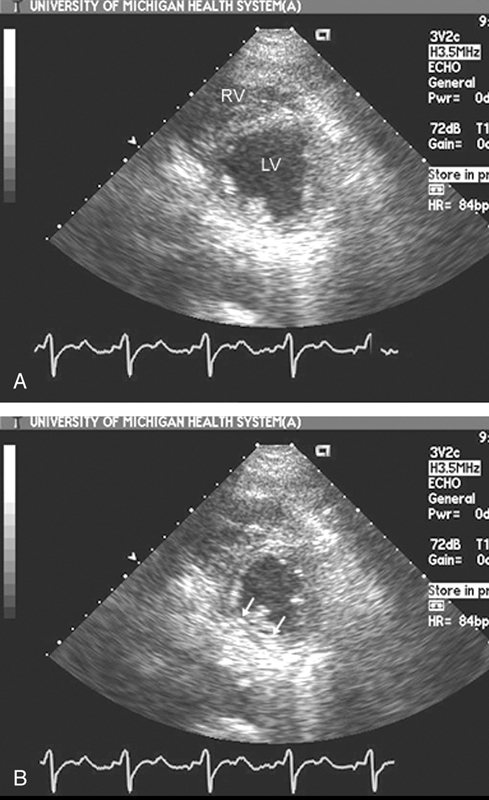

فحوصات تشخيصية لبعض امراض القلب والشرايين التاجية